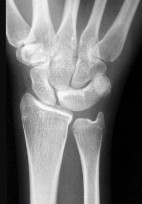

- الأشعة السينية (X-rays): هي الخطوة الأولى في تقييم الكسور، الخلوع، وتغيرات التهاب المفاصل. تساعد في تحديد مدى تدهور العظام والمسافات المفصلية. على سبيل المثال، تُظهر صور الأشعة السينية كسور السلاميات

، بالإضافة إلى علامات مثل "الدمعة الشعاعية" (Radiographic Teardrop) في الرسغ التي تمثل الزاوية الزندية الراحية الحرجة للكعبرة البعيدة

. - الأشعة المقطعية (CT Scan): توفر صوراً تفصيلية ثلاثية الأبعاد للعظام، وهي مفيدة جداً لتقييم الكسور المعقدة، مثل كسور العظم الخطافي (Hamate Hook Fracture) التي قد لا تظهر في الأشعة السينية العادية